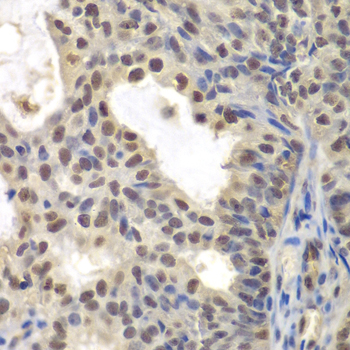

Immunohistochemistry of paraffin-embedded human oophoroma using CENPC antibody at dilution of 1:200 (400x lens).

Immunohistochemistry of paraffin-embedded human kidney cancer using CENPC antibody at dilution of 1:200 (400x lens).